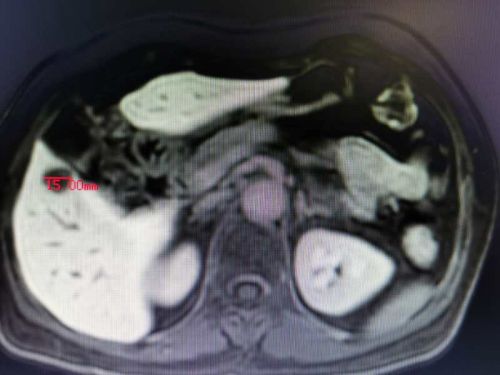

肝转移瘤

通过多项检查诊断技术全面评估肿瘤部位及患者全身状况, CTMRI(普美显)提示患者乙状结肠癌并肝脏寡转移瘤,结直肠肛门外科、肝胆外科、放射科、肿瘤科、病理科开展晚期结直肠癌MDT讨论认为,患者乙状结肠癌肝转移合并不完全性肠梗阻,暂不适合术前新辅助化疗,有乙状结肠癌和肝转移瘤同时R0切除手术机会,但同时切除手术难度及风险增加。

在与患者及家属充分沟通交流后,为患者制定术前处理、手术切除、术中监测、术后治疗和康复方案,由肖志刚主任团队施行目前结直肠癌专科最微创的手术方式——腹腔镜下乙状结肠癌根治性切除+S5段转移瘤切除,经阴道取出标本的NOSES手术(腹壁切口<1cm)。术中请肝胆外科杨建辉副主任医师同台行肝S5段转移瘤切除。手术过程顺利,患者术后无伤口疼痛,术后第1天下床活动,术后第2天肛门排气,第3天排便并恢复流质饮食,第6天复查CT腹腔干净并拔除腹腔引流管,第8天康复出院,电话随访患者状态良好。